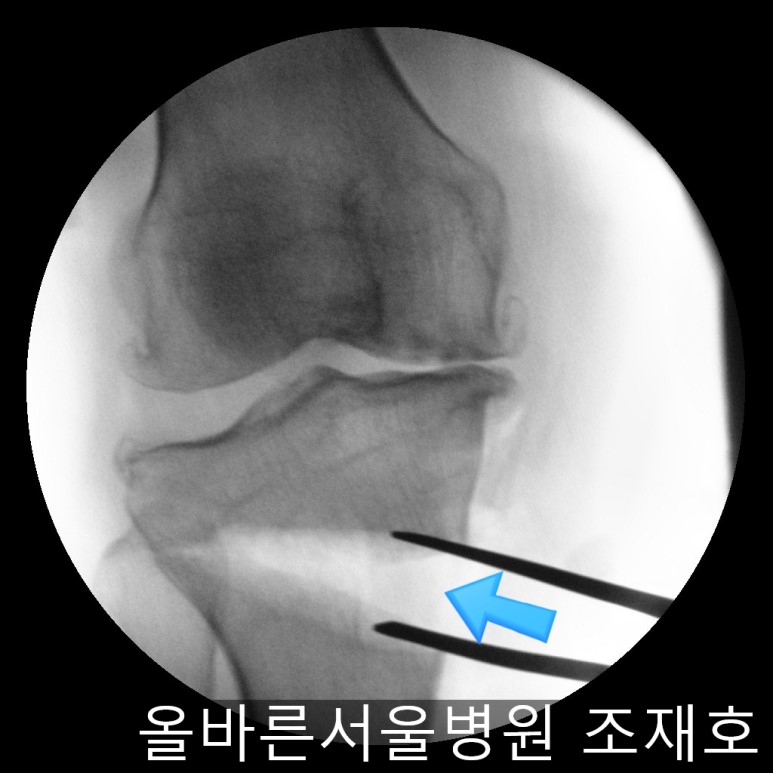

随后进行胫骨近端截骨术来矫正内翻变形。

需要进行20度矫正,因为没有这个度的矫正用模具,所以在手术前先计算内侧需要打开的程度。

如下图,适当的打开进行矫正。